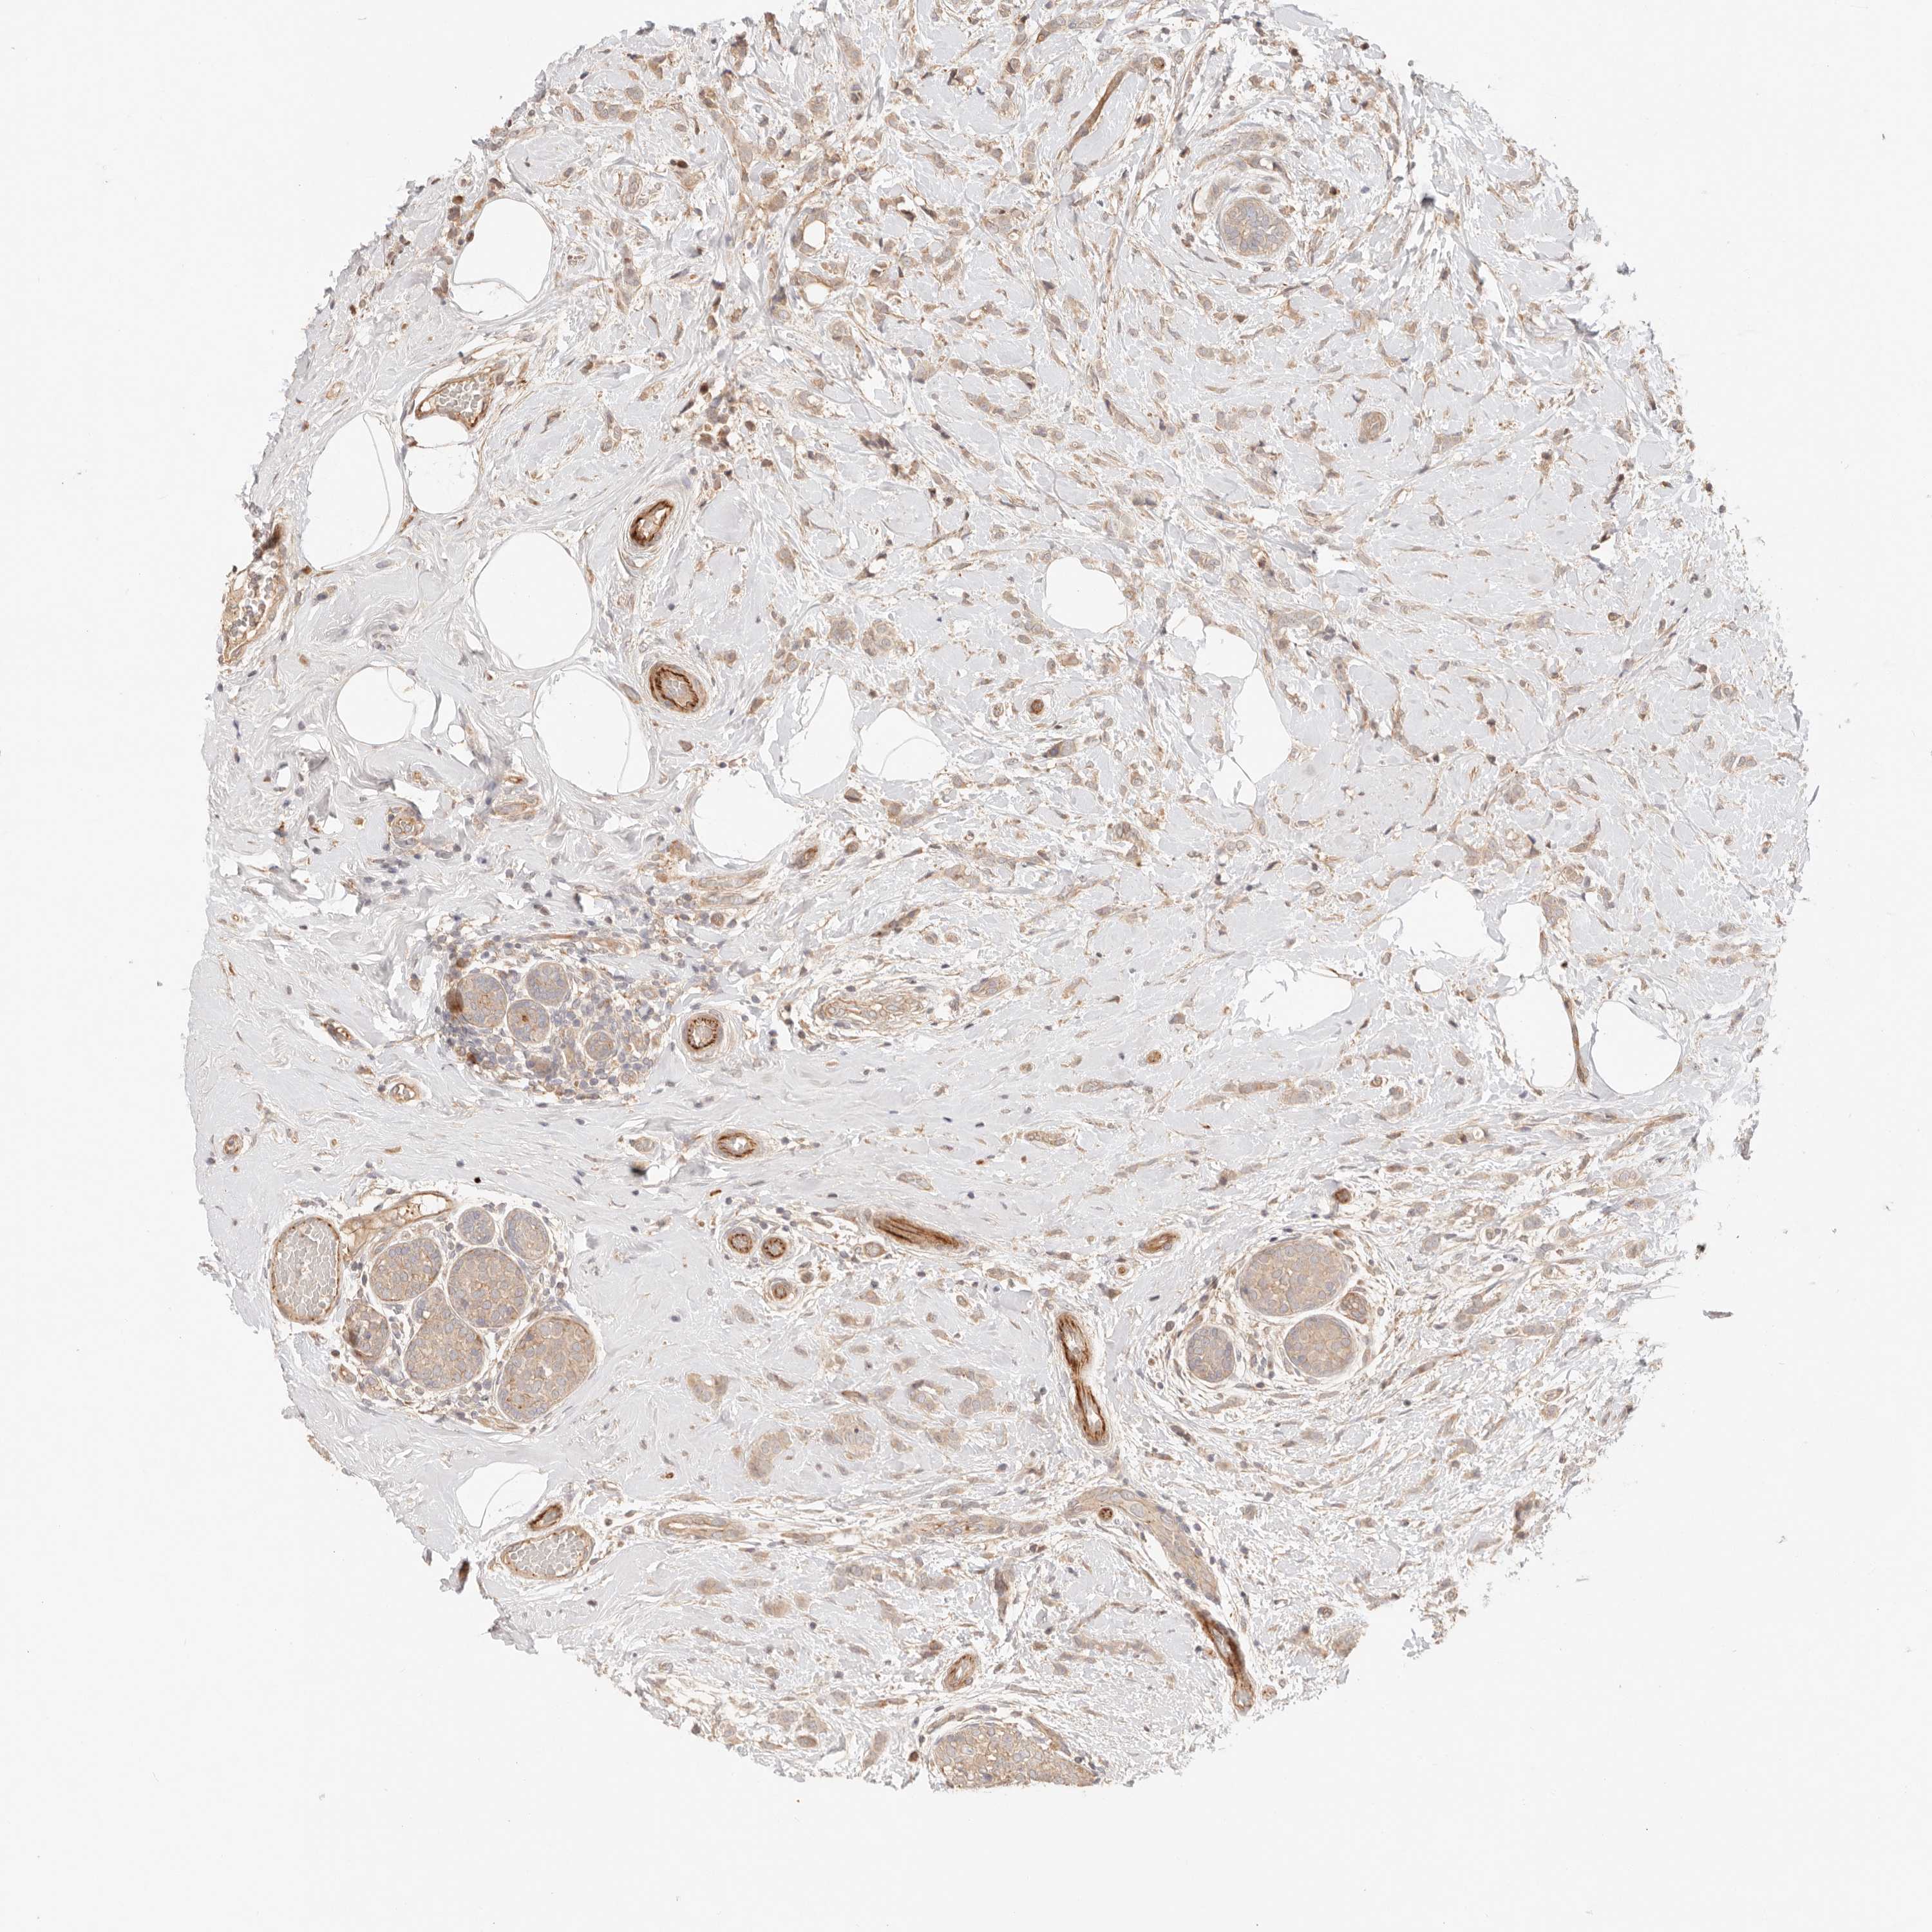

BRCA TCGA BRCA VALIDATION PROTEIN EXPRESSION